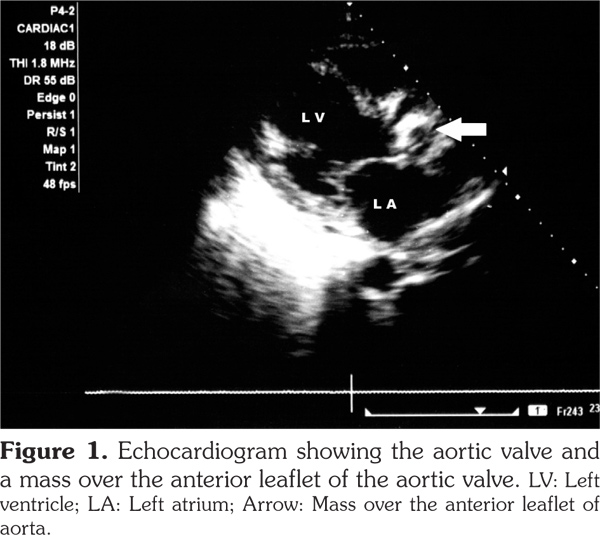

Cardiac involvement in granulomatosis with polyangiitis is rare. In this article, we describe a 47-year-old male case of aortic valve involvement with granulomatosis with polyangiitis. The patient had multi-system involvement in the form of pulmonary, renal, cutaneous involvement along with high levels of anti-proteinase 3. Echocardiography revealed a mass over the anterior leaflet of aortic valve with a mild aortic stenosis and aortic regurgitation. We suggest that clinicians should perform a thorough cardiac examination for any possible valvular involvement in patients with granulomatosis with polyangiitis.

The patient had normocytic normochromic anemia with a hemoglobin level of 8 g/dL, white blood cell count of 14000/mm3 with 80% neutrophils, serum urea value of 80 mg/dL, and serum creatinine value of 2.5 mg/dL. Serum electrolytes and liver function test results were normal. Urinalysis examination revealed protein 3+, and 15-20 red blood cells per high power field. Twenty-four-hour urine protein was 1.2 grams. Abdominal ultrasound revealed enlarged kidneys with increased echotexture and altered corticomedullary differentiation. Thoracic X-ray demonstrated bilateral pulmonary infiltrates, while computed tomography revealed bilateral patchy opacities with thickening of the right horizontal fissure and bilateral alveolar infiltrates. Echocardiography also revealed a mass over the anterior aortic valve with mild aortic stenosis and moderate aortic regurgitation (Figure 1). Anti-neutrophilic cytoplasmic antibody (ANCA) serology showed a markedly increased level of anti-proteinase 3 (anti-PR3) (31 IU/ml, cut off ≤3.5 IU/ml), and anti-myeloperoxidase (anti-MPO) level of 2.1 IU/ml (cut off ≤9 IU/ml). Blood cultures were sterile. Antinuclear antibodies, human immunodeficiency virus, hepatits B surface antigen, hepatitis C virus serologies and sputum for acid-fast bacilli were negative. A preliminary diagnosis of GPA with acute nephritis and probable alveolar hemorrhage were made based on the possibility of concomitant infective endocarditis/involvement due to GPA. The patient was firstly treated with broad-spectrum antibiotics. However, after three days of no response to the antibiotic therapy, the patient was started on pulse methylprednisolone doses of one gram per day for five days along with pulse cyclophosphamide of 750 mg, and the antibiotics were also continued. The patient improved over a period of one week, and his hemoptysis stopped. His repeat urea was 60 mg/dL, and serum creatinine level was 1.5 mg/dL. The patient was discharged with prednisolone 60 mg per day and was asked to apply to the outpatient department for the next pulse of cyclophosphamide. However, the patient did not report back and was lost to follow-up.

Our patient presented with predominantly renal and pulmonary involvement. Besides, in the course of investigation, he was found to have a valvular lesion in the form of aortic valve mass. We considered the possibility of the mass being a vasculitic lesion in view of the patient’s high disease activity in other organs including the lungs, kidneys and skin, and high titers of anti-PR3 antibodies. Additionally, no organism grew in blood cultures, and the patient responded to high doses of parenteral steroids.

Thus, we report a very rare occurrence of an aortic valve mass in a patient of GPA which we presume to be a lesion secondary to GPA. The pointers in favor of the mass being secondary to GPA were (i) having no response to initial antibiotic therapy, (ii) sterile blood cultures, and (iii) pulmonary involvement in the form of pulmonary hemorrhage and hemoptysis. Also, the patient responded to the immunosupression rather than deteriorating which would have been the case if the patient had underlying subacute bacterial endocarditis and sepsis. However, our report is limited by the fact that the patient was lost to follow-up. Besides, the histopathology of the mass lesion was not available. We believe that all the patients with GPA need to undergo echocardiography for any cardiac involvement.